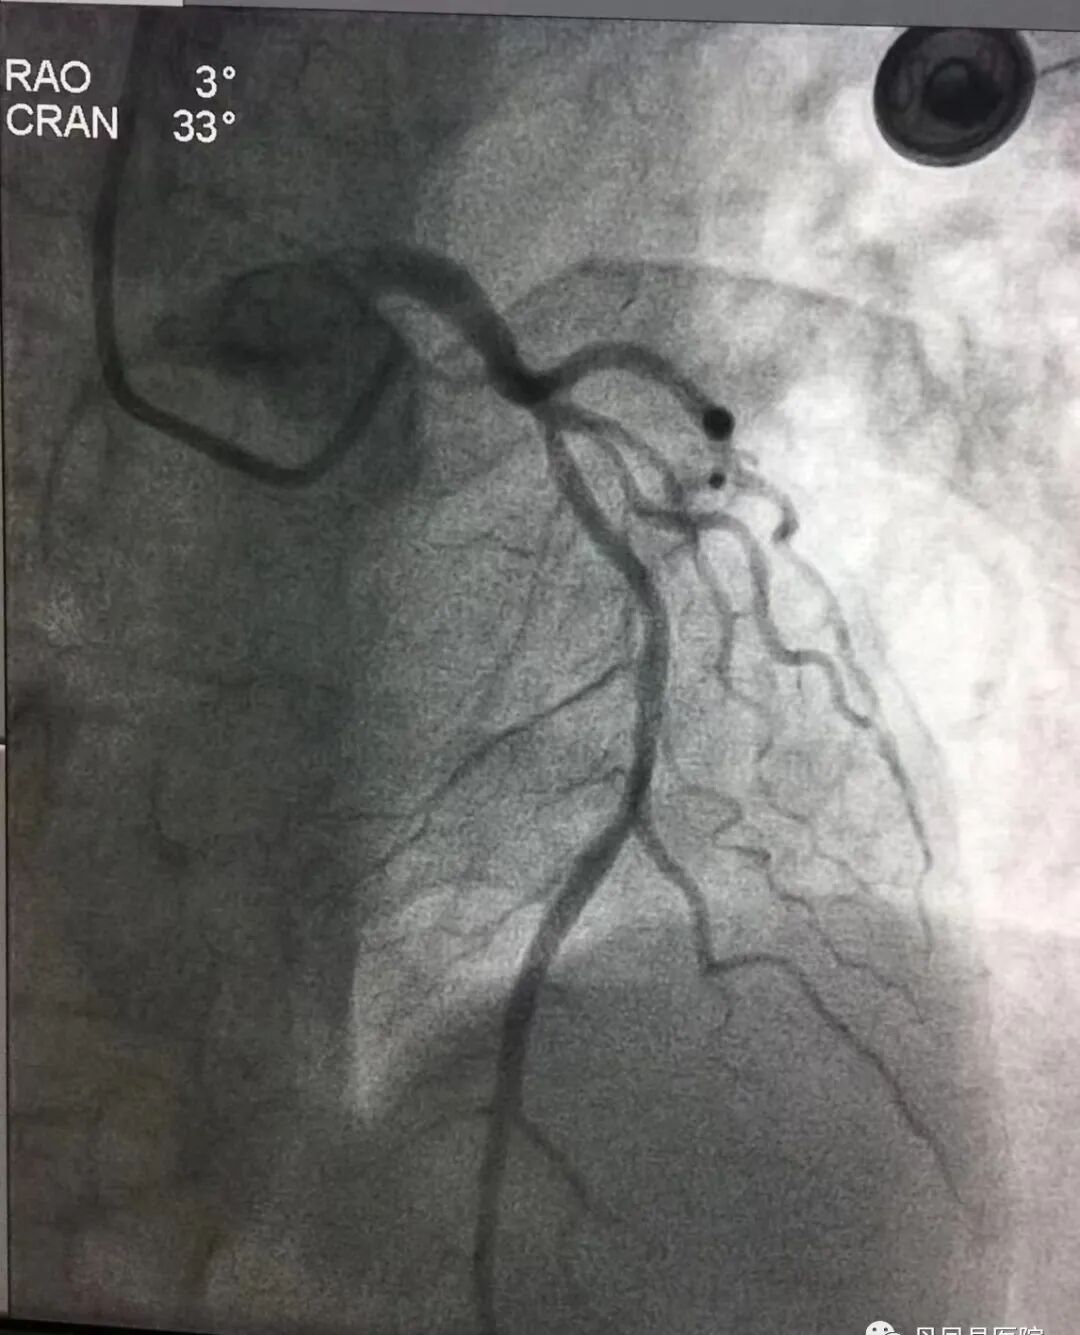

“准备除颤仪,立即口服心梗“一包药”,建立静脉通路,静脉注射普通肝素4200U!”刘大夫有条不紊的指挥,护士们迅速执行。9:20在经过患者家属知情同意并进行溶栓筛查后,胸痛中心医护人员给予患者注射用尿激酶原50mg静脉溶栓治疗,9:55溶栓结束。在心血管内科陈经鹏主治医师协助下,观察患者生命体征平稳后,联系商洛市中心医院胸痛中心,转运患者绕行急诊科,直达导管室。经造影证实患者属前降支病变,且血管再通,提示溶栓非常成功。

图为溶栓后冠脉造影图像